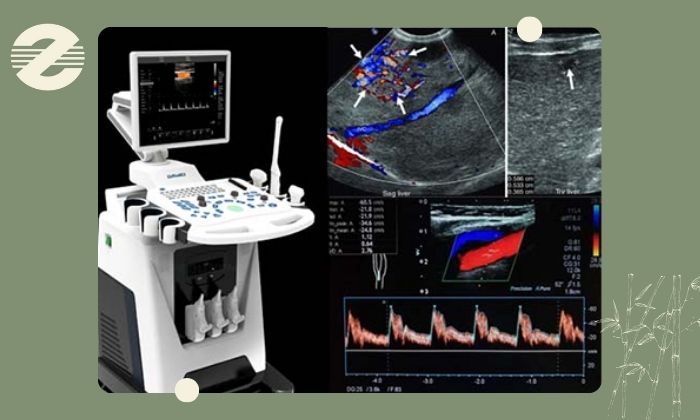

در این مرکز دستگاههای نسل جدید سونوگرافی مطابق استانداردهای جهانی مورد استفاده قرار میگیرند. این تجهیزات قادرند در مدت زمان کوتاه تصاویری با وضوح بالا از جریان خون در عروق بدن تهیه کرده و با تحلیل پیشرفته دادهها جزئیترین اختلالات عروقی و قلبی را نمایان سازند.اطلاعات جمعآوری شده توسط تیم پزشکی مرکز بهصورت تخصصی تفسیر و گزارش میشوند تا بهترین مسیر درمان برای هر بیمار انتخاب شود.